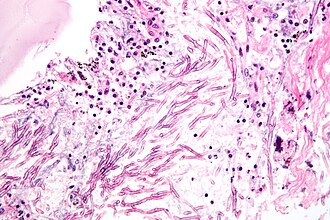

Mucormycosis

General

- Causative organism: Mucorales.

- Kingdom: Fungi.

- AKA Zygomycota (zygomycosis).

- Associated with diabetes, immunodeficiency.

Microscopic

Features:[5]

- Branching hyphae with variable width.

- Granulomata associated.

Notes:

- Not septated.

- Branching angle typically ~90 degrees.

Images

- Zygomycosis.jpg

Zygomycosis - cytology. (WC)